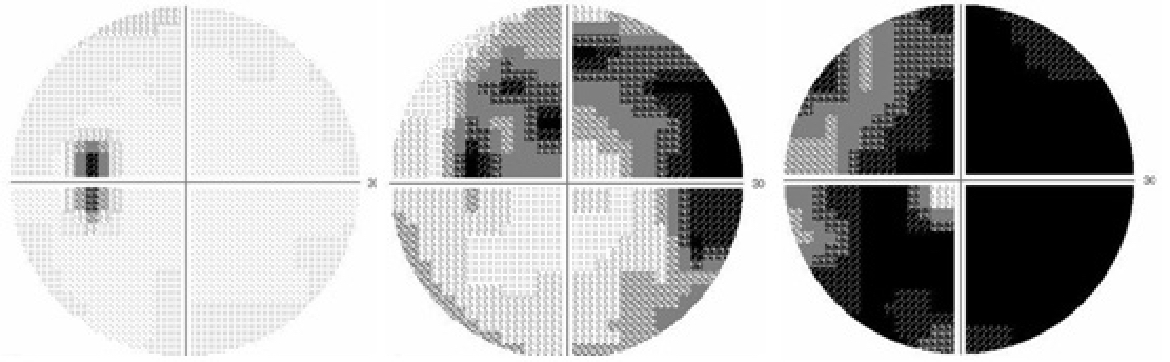

図1. 光干渉断層計

最新のOCTで診断された極早期の緑内障

右眼(むかって左側)は極初期視野障害期

左眼(向かって右側)は前視野障害期

図2. ハンフリー視野検査

黒くなった部分に視野障害があります。左から正常、中期視野障害、末期視野障害で黒い部分が増加しています。